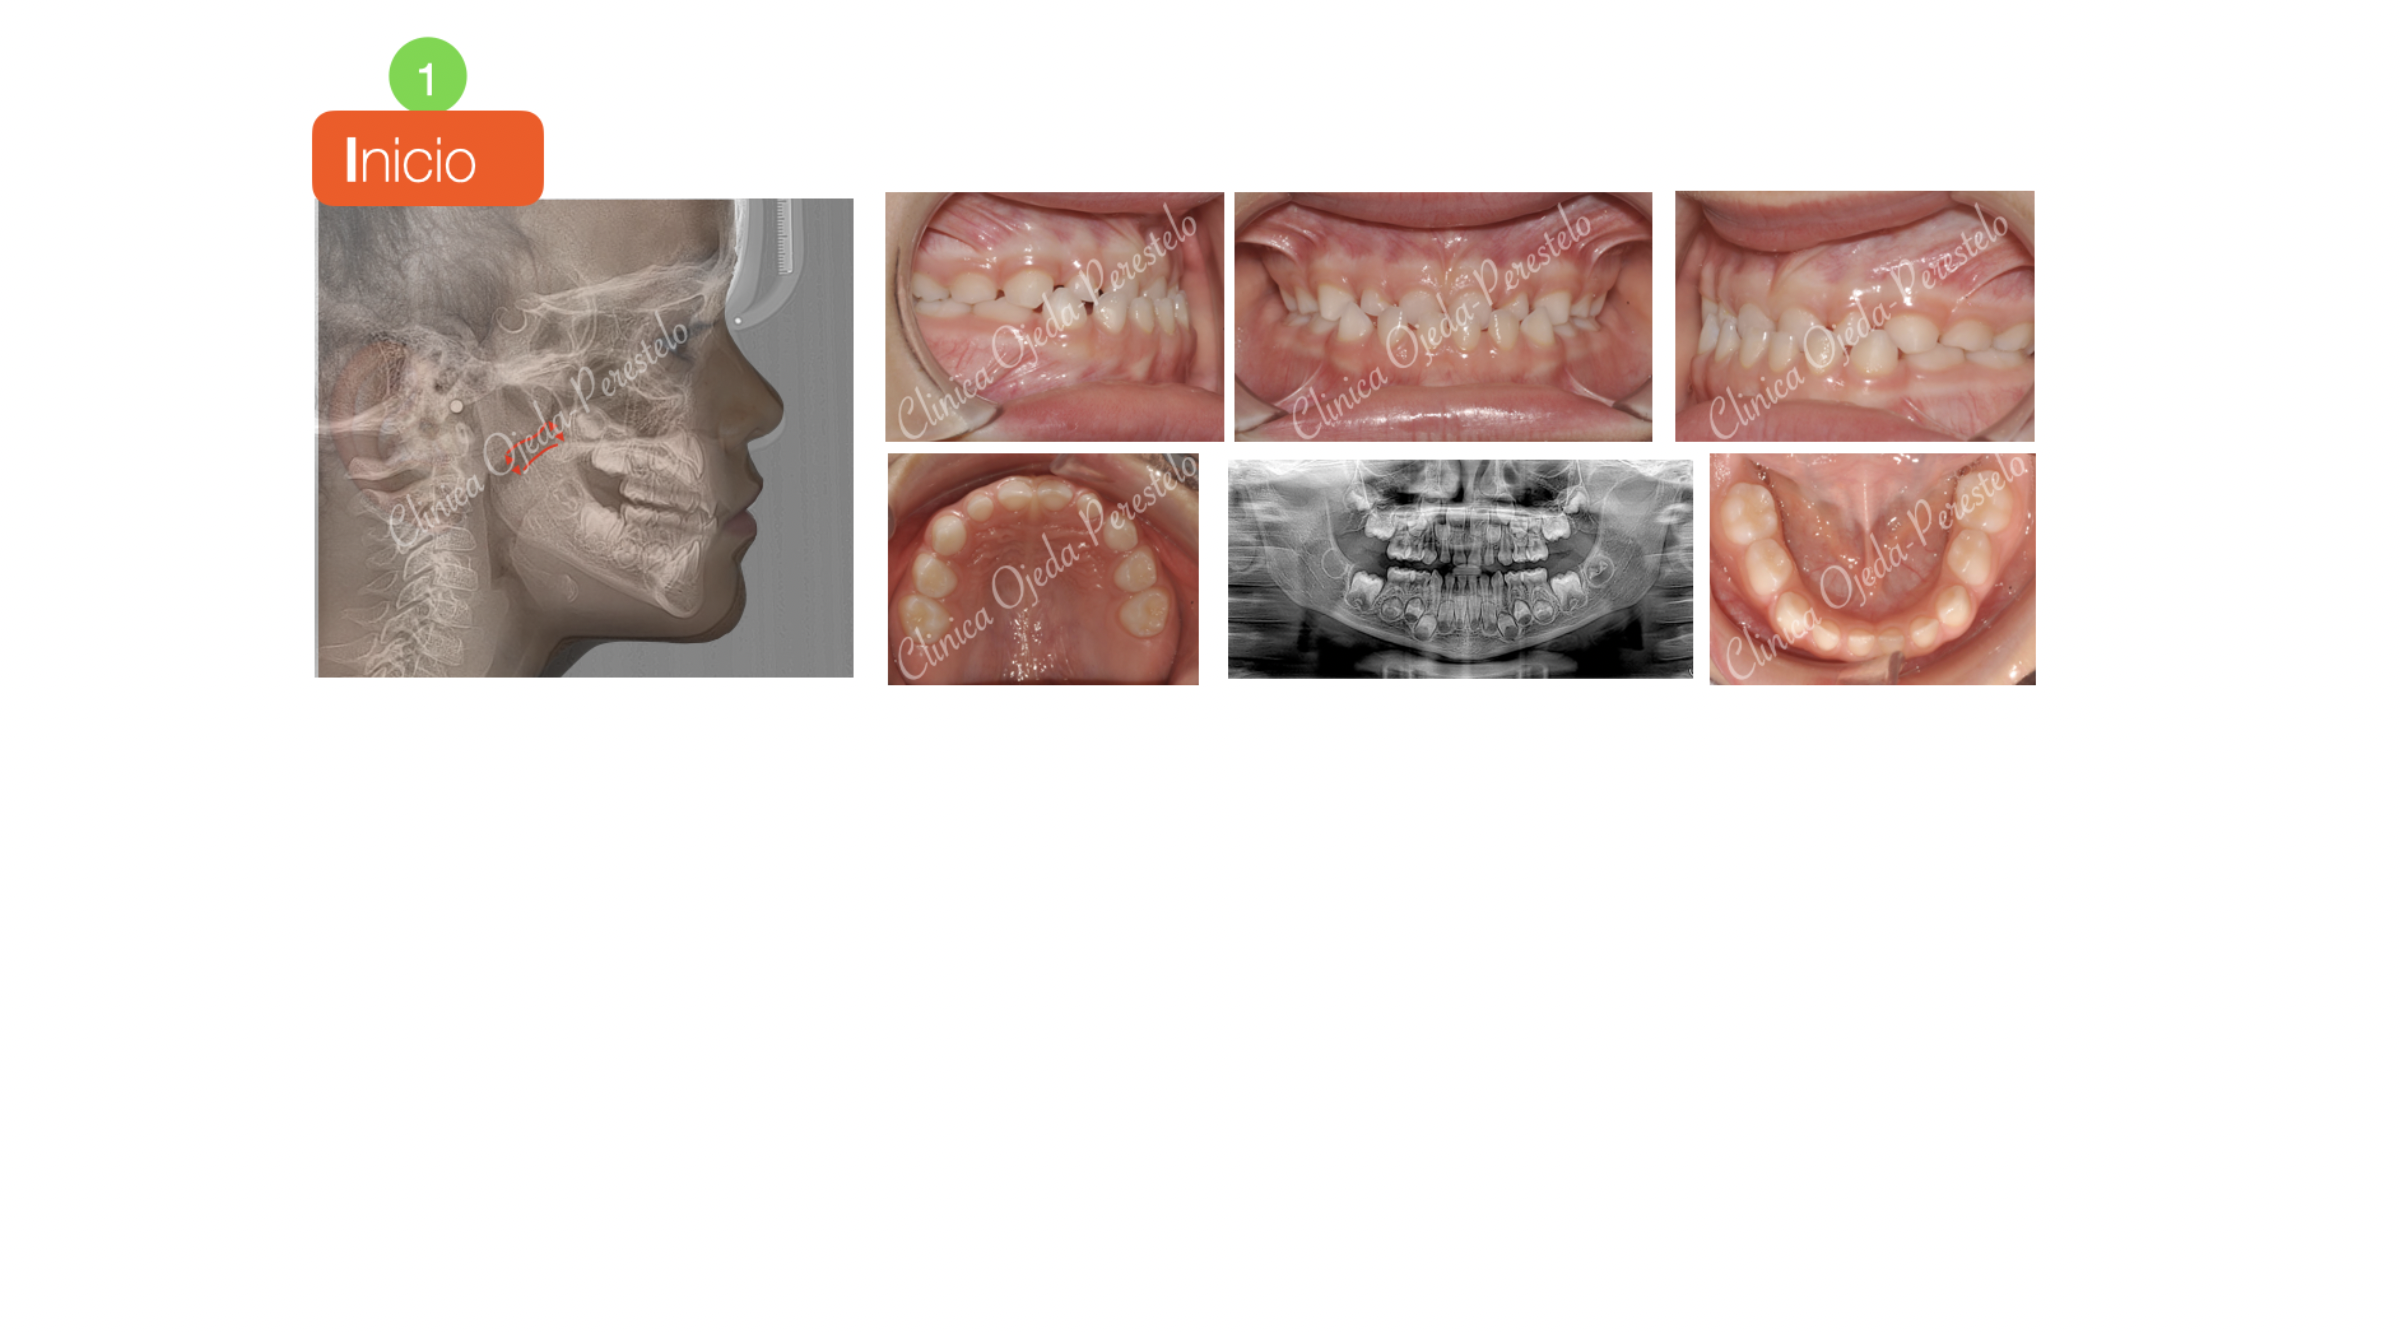

Clase III esquelética en dentición temporal

Paciente niña en dentición temporal con clase III esquelética tratada con Ortopedia (Disyunción Maxilar + Máscara Facial). Este tipo de alteraciones óseas es importante tratarlas a edades tempranas a efectos de conseguir una respuesta lo más eficiente posible. En este caso la expansión y tracción anterior del Maxilar (12-14 horas/diarias) ha sido posible en 6 meses dada la edad y la colaboración de la paciente.

Quisieramos destacar la mejora experimentada en la sonrisa, la función masticatoria y en la eliminación de los ronquidos debido al aumento de la vía aérea ( Nasofaringe) producido por el avance del Maxilar.